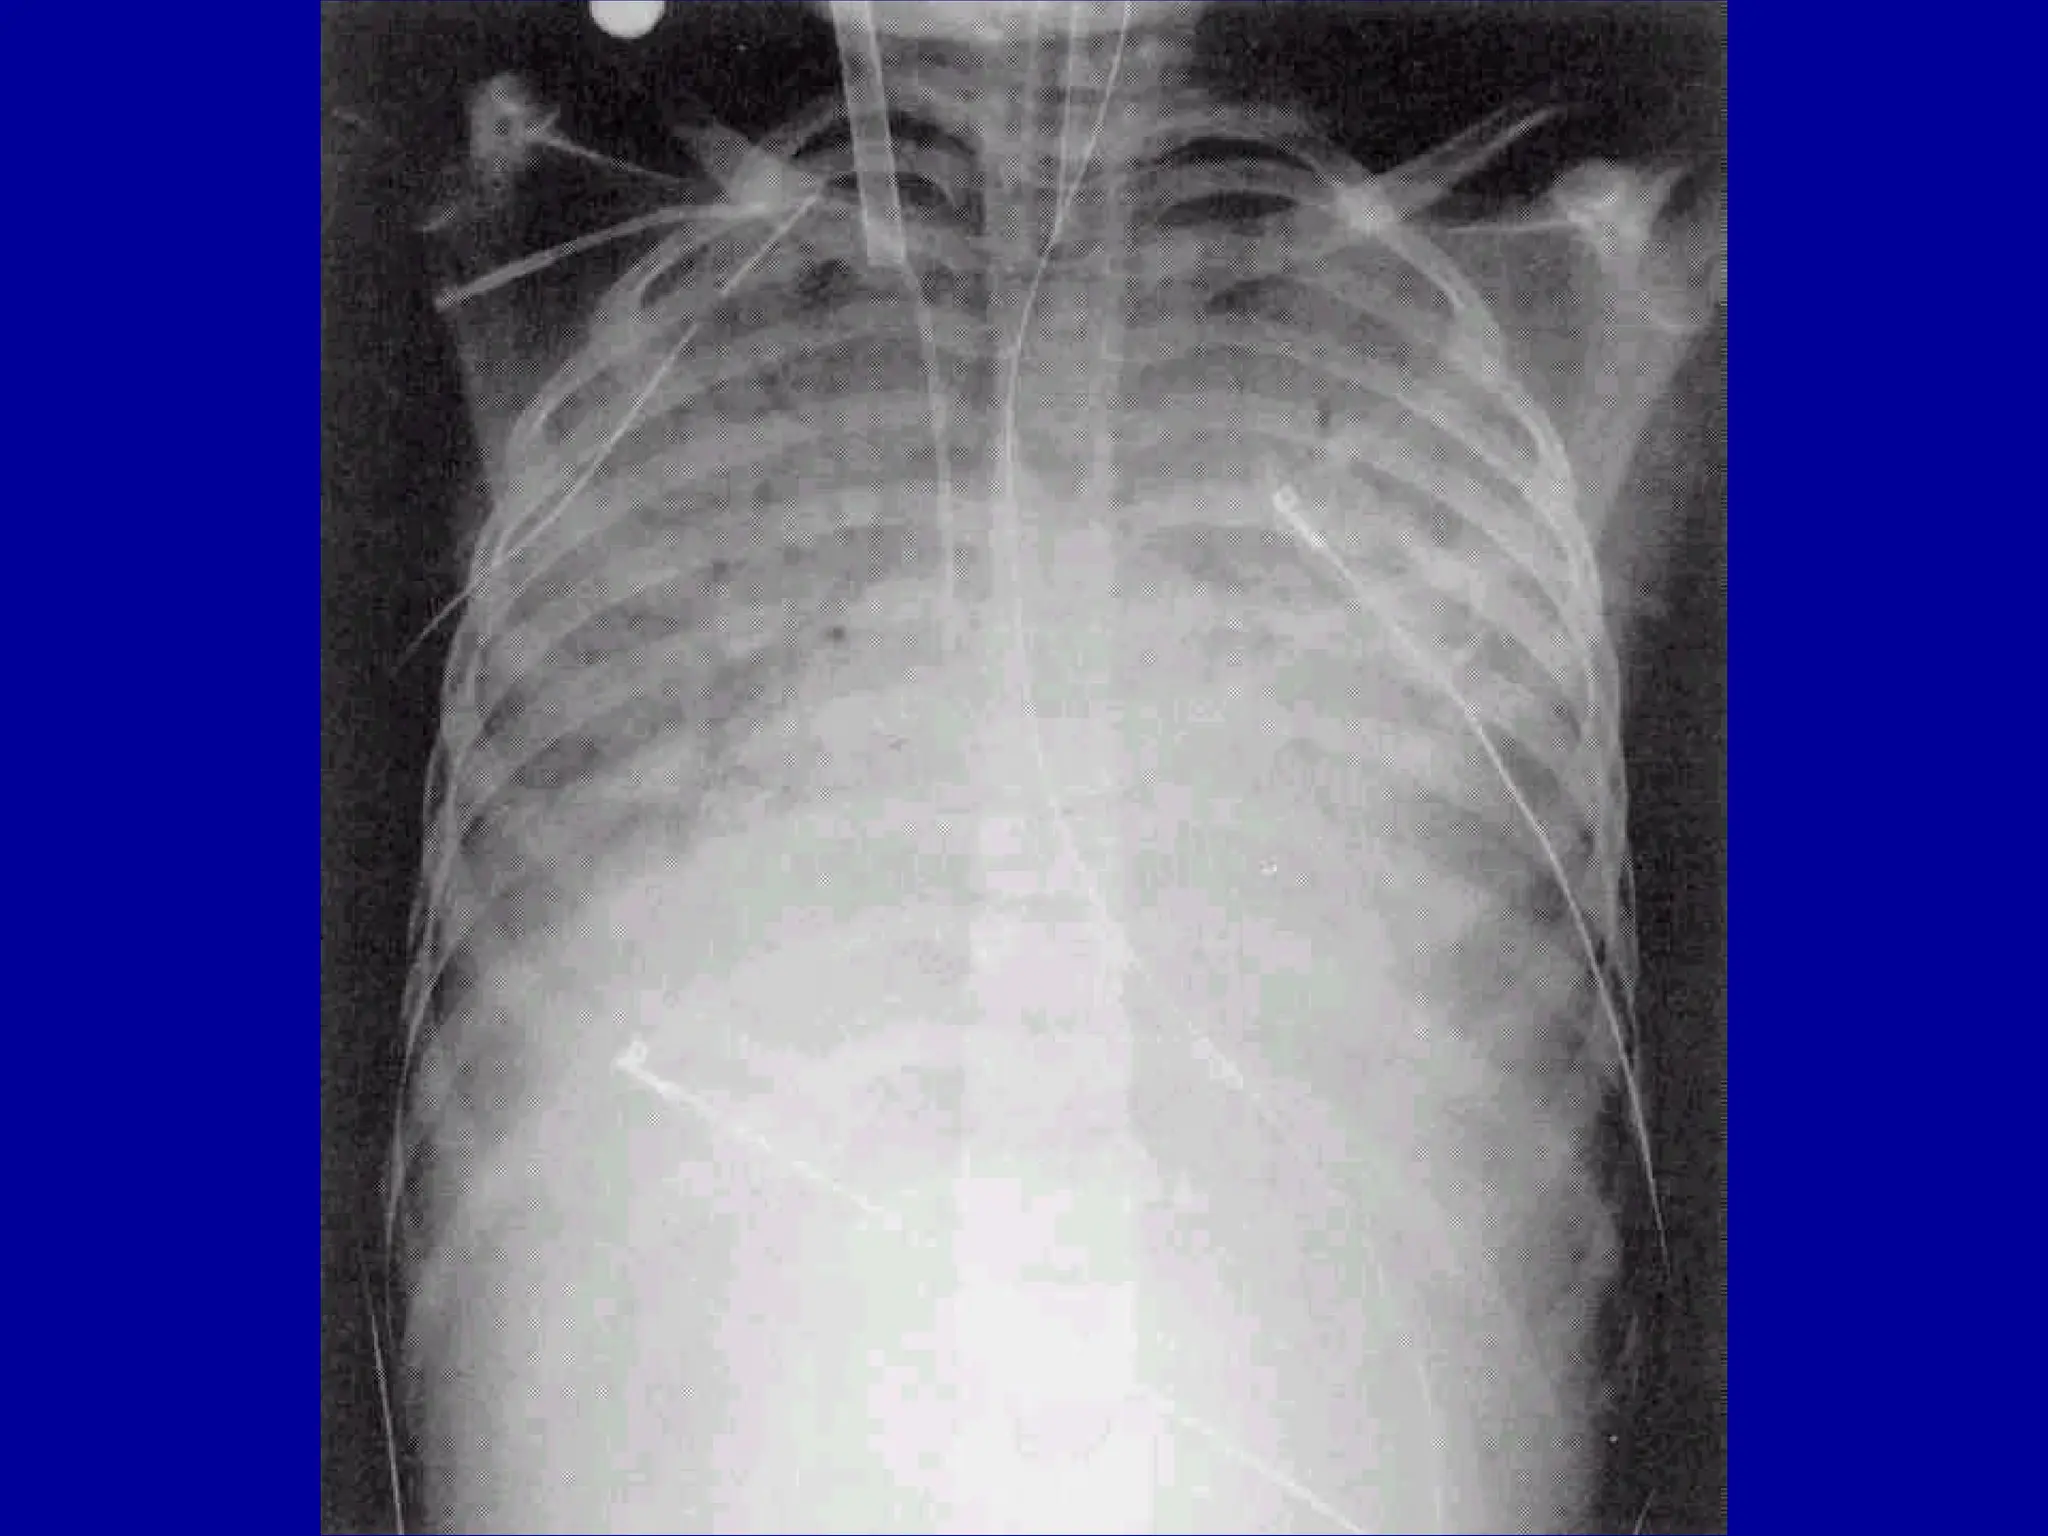

Other Laboratory Findings in ARF

CXR Abnormalities